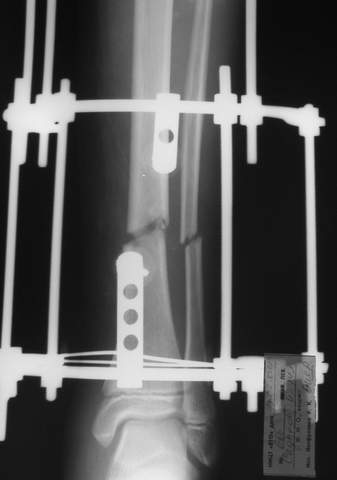

В аттачте № 3 - один из примеров полукольцевого аппарат...

Это уже я баловался.

Итог? Работы больше (по времени и

интраоп "подгонке"), срастается также, а особого преимущества по сравнению с

"чиста" кольцевым (вес, удобство ношения и пр.) - я, по крайней мере,

не нашел.

Теперь не балуюсь.

Может быть зря?

;-)